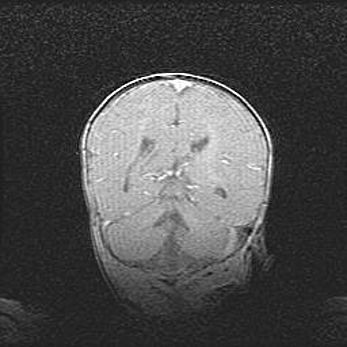

Лейкомаляция с кистозно-глиозной дегенерацией головного мозга.

Возраст: 2 месяца 25 дней

Вес: 6400 г

Окружность головы: 40 см

Срок гестации: 41 неделя

Лейкомаляцию относят к ишемически-гипоксическим повреждениям головного мозга, диагностируемым у новорожденных. При лейкомаляции в головном мозге обнаруживают очаги некроза, возникшие после тяжелой гипоксии и нарушения кровотока. В процессе морфогенеза очаги проходят три стадии: 1) развития некроза, 2) резорбции и 3) формирования глиозного рубца или кисты. Перивентрикулярная лейкомаляция (ПЛ) встречается примерно в 12% случаев среди новорожденных, обычно – у недоношенных детей, причем, частота ее зависит от массы, с которой младенец появился на свет. Наибольшее число малышей страдает лейкомаляцией, если масса при рождении 1500-2500 г.